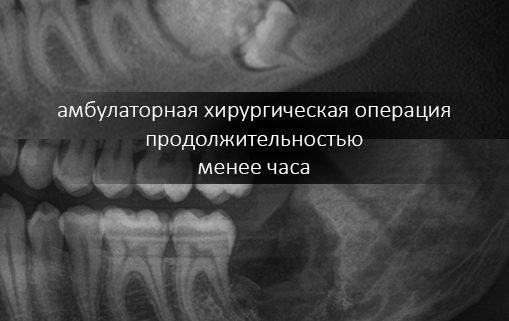

Между тем, эта остеопластика, хоть и считается одной из самых сложных имплантологических операций, для пациента очень даже комфортна и совершенно безопасна. С современными методами, инструментами и материалами, риски осложнений при подобных операциях удается удерживать на уровне 1-2%, что, согласитесь, очень круто (для сравнения, осложнения при лечении кариеса составляют немногим более 10%).

С той же остеопластикой — чаще всего ее проводят из-за выраженной атрофии костной ткани, которая вызвана длительным отсутствуем зубов. Если бы пациенту вовремя (в идеале — сразу) поставили импланты и провели протезирование — остеопластики удалось бы избежать. А, если вовремя заняться лечением зубов — возможно, был бы шанс избежать их удаления и последующей имплантации. - Не экономьте на квалификации и опыте врача. Ищите компетентного специалиста, применительно к Вашему случаю.